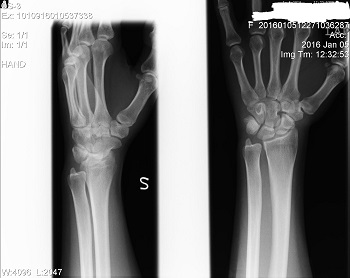

Също така ви изпращам първоначалната снимка на лявата ръка, както и снимката на двете ръце, направена преди около 2 седмици, ако може да ми кажете какво според вас е състоянието на ръцете ми и дали може да се определи дали това образувание на лявата ръка е хематом, ганглион или нещо друго.

- Img0001.jpg (26.21 KiB) Прегледано 1751 пъти